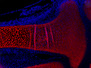

Without the blue and red fluorescent colours that have been used to label these blood vessels, this entwined pair would be difficult to tell apart. Arteries (red) and veins (blue) are both built to transport blood, but they are designed to do different jobs. While arteries have muscular walls to withstand high blood pressure and transport oxygen laden blood from the heart, veins have thin walls and ‘inner tubes’ with a larger bore to transport blood carrying waste products and carbon dioxide away for disposal. Microscopic branches of veins and arteries meet deep inside tissues. If this microcirculation becomes damaged, tissue is starved of vital oxygen forcing new vessel branches to grow (a process called angiogenesis). Scientists are now using these contrasting colours to track new vessel growth as it happens in live animals, providing them with a clearer picture of how chronic inflammatory disorders such as arthritis develop.